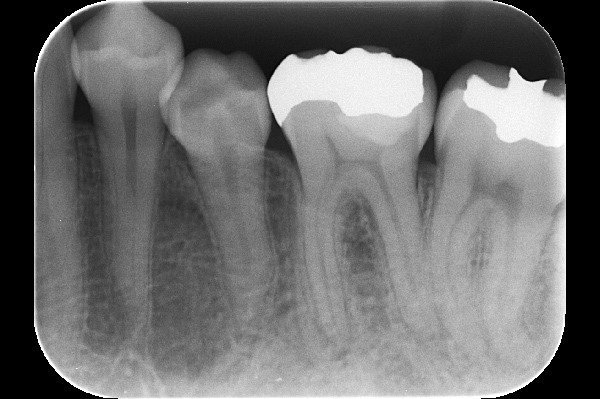

2.術前のX線写真

レントゲン写真では大きな問題が無いように見えますが、金属の土台が歯の生えている方向と違う方向に入っていることがわかります。

11.穿孔部封鎖後のX線写真

後ろの根の穴が適切な材料で埋められている様子が確認できます。外との遮断を適切に行うことが重要です。

16.セット時のX線写真

根の内側の封鎖をした部分は安定しているようです。

18.治療後3年6ヶ月後のX線写真

こちらは3年6ヶ月のフォローアップ時のX線写真です。問題なく経過しています。